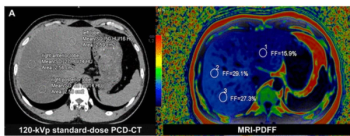

Irrespective of differences with radiation dosing and tube voltage, obtaining CT-derived fat fraction from photon-counting detector CT provides consistently comparative results to MRI-derived proton density fat fraction assessment, according to new research.